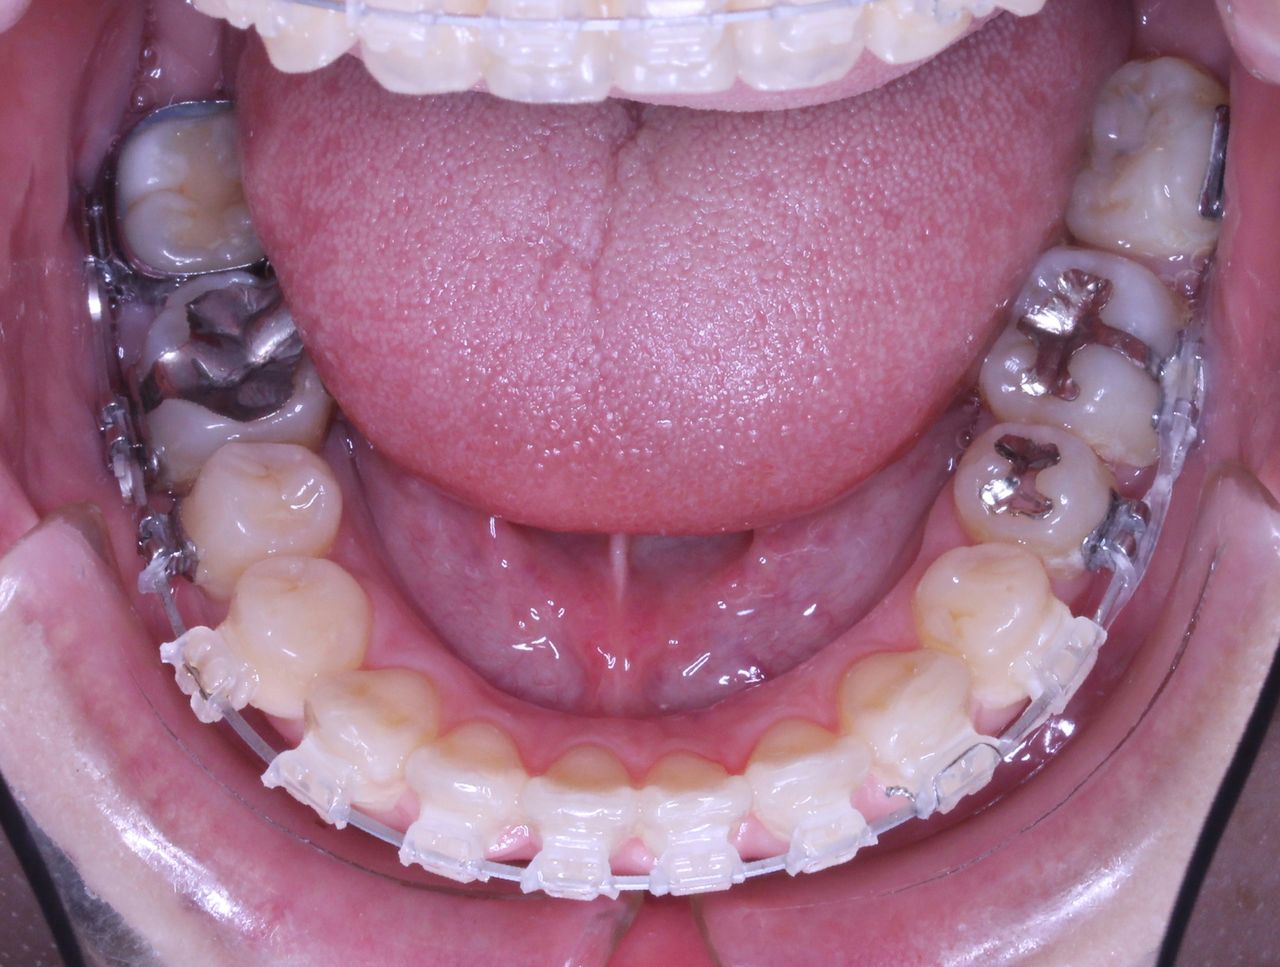

虫歯治療はきちんとされてますが、奥歯に全部銀歯の状態の歯があります。

当然、神経もない歯です。治療されたのはだいぶ前とのことでした。

それでは治療経過です

少し経過が進みました